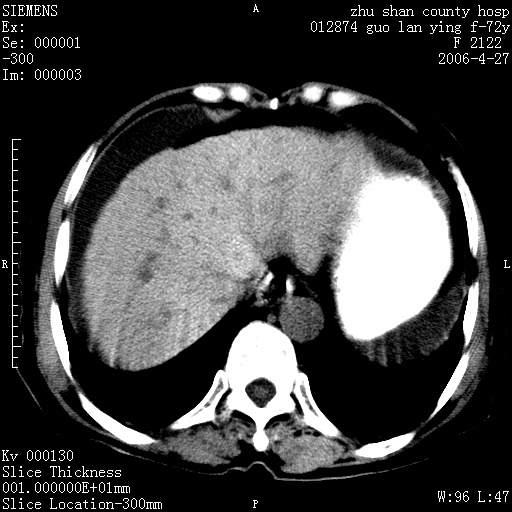

病人 女性 72岁 b超要求ct检查!

平扫所见:胆囊区两点壮高密度影,灶周有伪影{请问楼主患者有手术病史?}。肝实质内未见明显异常{建议强化或mri}.腹腔有少量积液,脾明显增大.右肾形态似不规则?

腹腔内示积液征,脾脏略增大,肝脏由于运动伪影较多,影响观察,内未见明显高密度区,胆囊内示两处高密度结石。胃窦部壁轻度增厚。另外,肝脏的前缘似有游历气体。不知病人的临床如何?有必要做胃的检查,还有,看看骨窗是否有腹腔游离气体还是肠管影响的。

如果b超对肝脏有怀疑,肝脏的增强扫描还是尽量去做。

肝脏缩小,脾脏增大,肝脾外缘及胆囊窝液性密度影,肝脾ct值正常,胆囊区见两个类圆形高密度影,下腔静脉前方类圆形软组织密度影为肝脏岛叶,胃幽门区见软组织密度影,十二指肠钡剂充盈不好.

1:腹水2:胆囊结石3肝硬化?(不确定,请结合临床)4幽门区占位?(建议胃肠透视)

肝硬化,脾大,少量腹水

肝硬化、脾肿大,腹水,胆囊区高密度影(结石或异物),是否有外伤史

肝硬化、腹水、脾大,胆囊结石可以肯定。只是肝右叶两个低密度有必要增强确定一下;排除小肝癌。

谢谢牟教授在百忙之中还认真的点评我的帖子!也谢谢大家的鼎力相助,此病人是我们医院护理部主任的母亲!病人以前无特别不舒适!昨天b超后发现有问题!做ct的目的在于排除肝内占位性病变,此病人以前无手术外伤史.